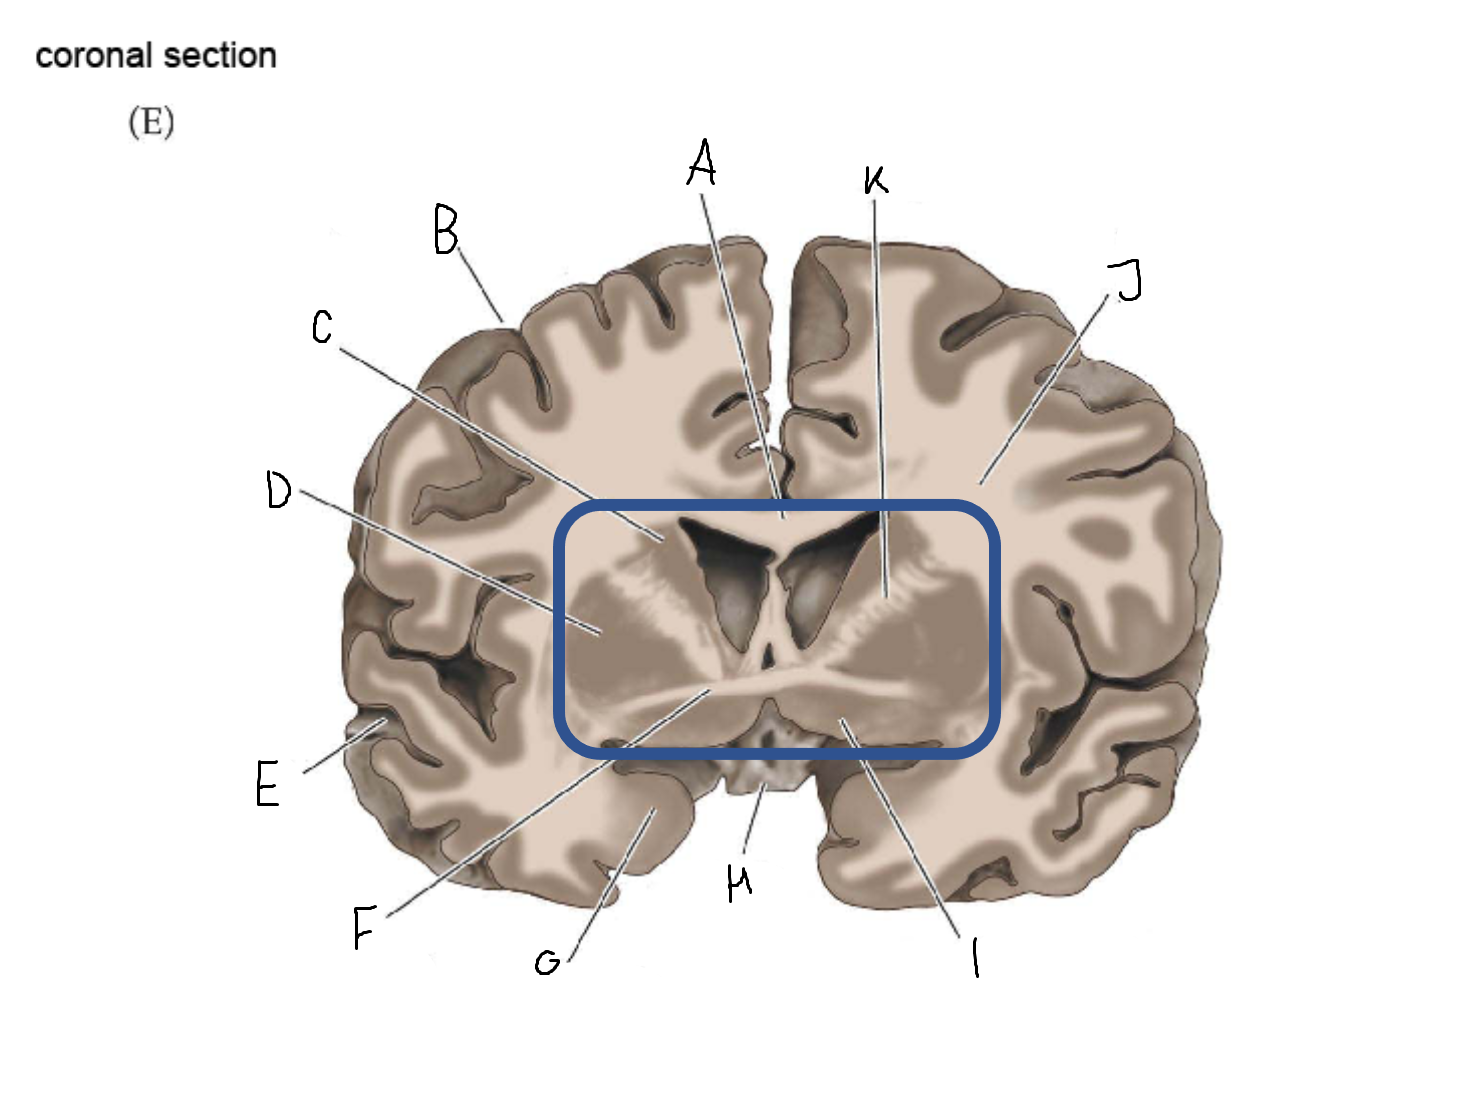

A

corpus callosum

B

lateral ventricle

C

internal capsule

D

third ventricle

E

tail of caudate nucleus

F

lateral ventricle

G

hippocampus

H

mammillary body

I

fornix

J

globus pallidus

K

putamen

L

caudate

M

thalamus

N